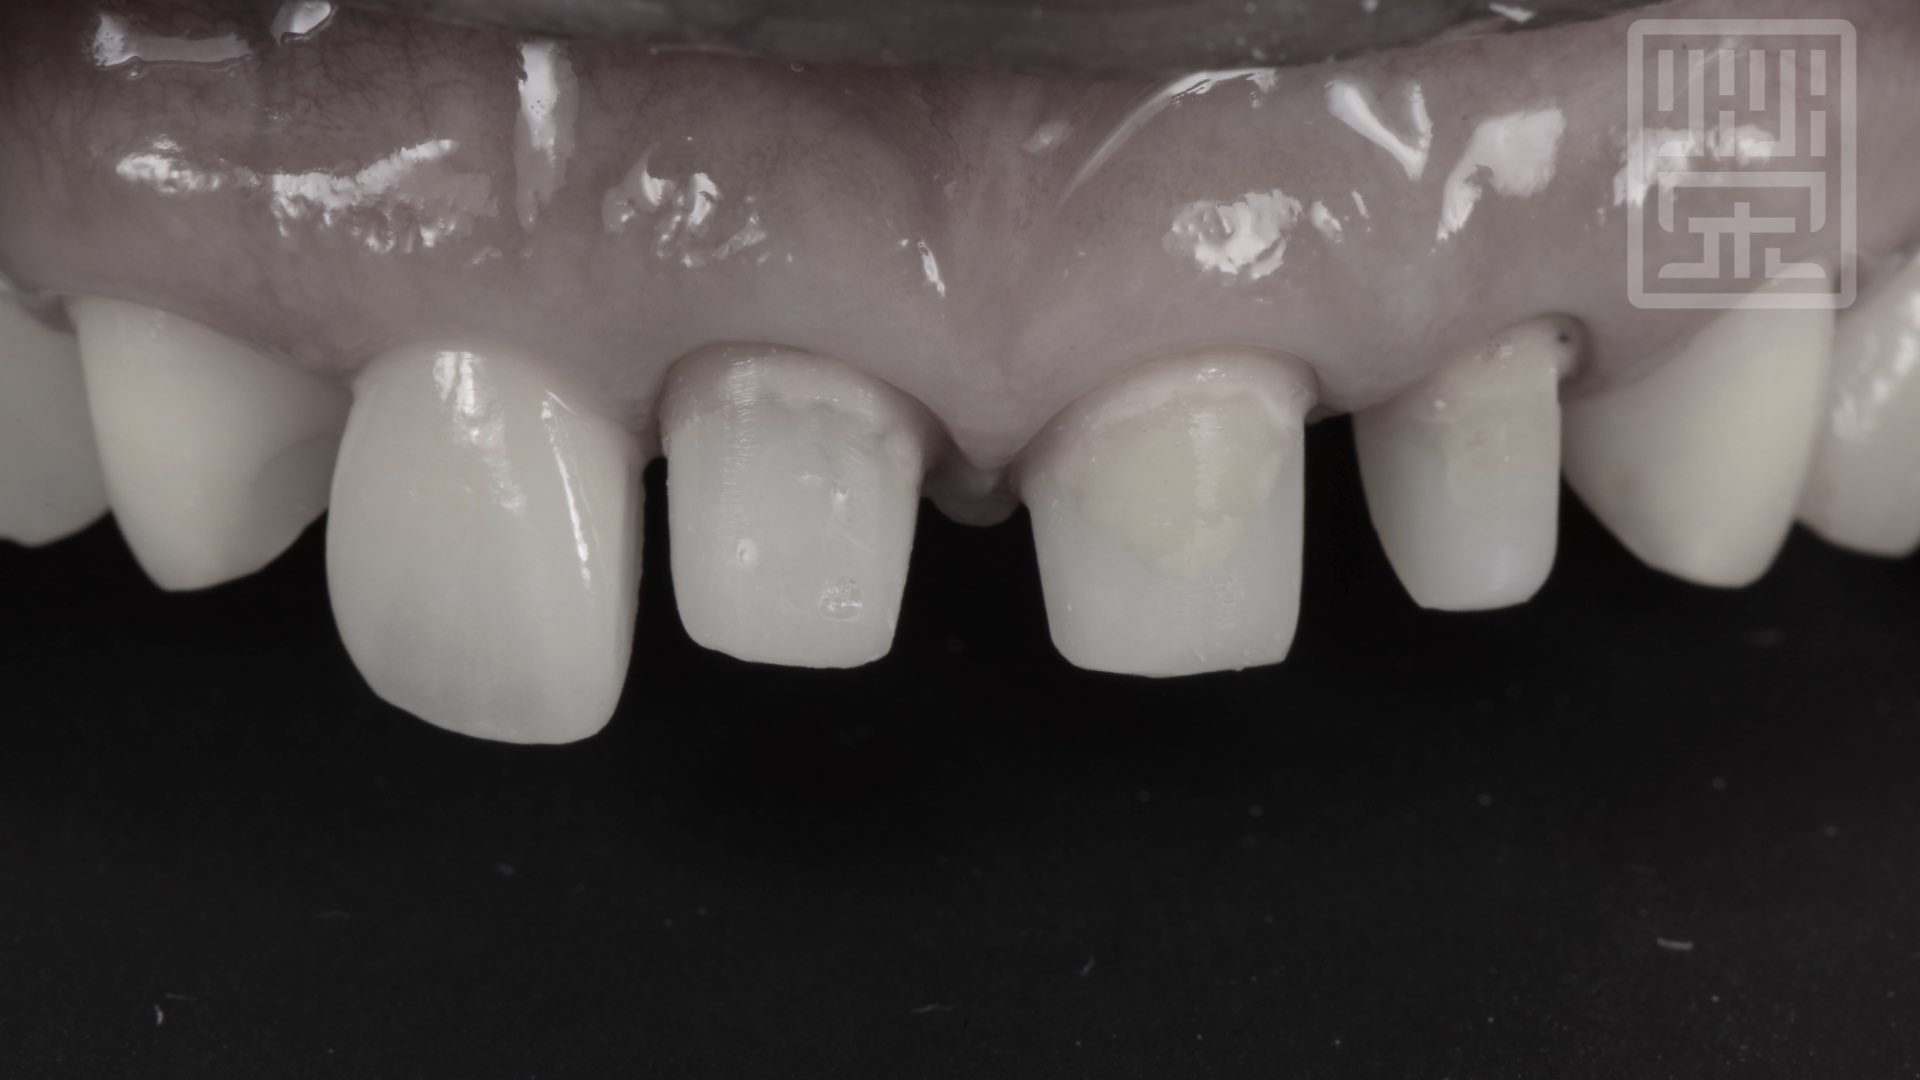

健康的植牙周圍牙齦

植牙全瓷冠